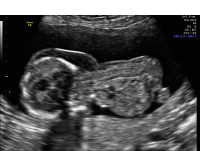

Cystic hygroma sagittal

A cystic hygroma refers to an excess fluid accumulation in the space behind the fetal neck and back. Usually observed via ultrasound examination in the first trimester, it affects approximately one in 100 pregnancies.